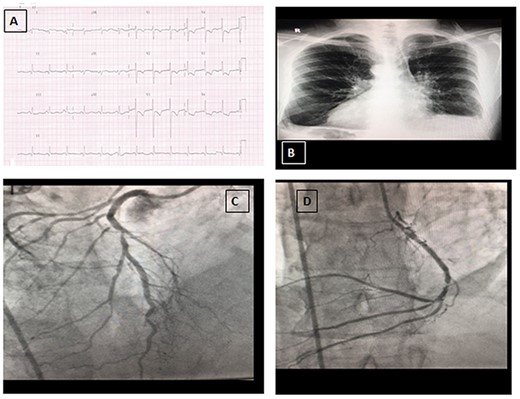

A 57-year-old man known to have dextrocardia and SI totalis presented with anterolateral non-ST elevation myocardial infraction and pulmonary oedema. He had dyspnoea with New York Heart Association class III symptoms. His past medical history was significant for hypertension and type II diabetes mellitus. He was an ex-smoker for the past 2 years. There was no family history of heart disease. The apex beat was palpated on the right side, and a pan-systolic murmur was heard best at the apex. ECG showed depressed ST segment and T waves in leads V1-V6 (Fig. 1A). Chest radiography showed dextrocardia and cardiomegaly (Fig. 1B). Coronary angiography showed triple vessel disease (Fig. 1C and D). Transthoracic echocardiography revealed severe left ventricular dysfunction (ejection fraction 30%), severe global left ventricular hypokinesia and severe ischemic mitral regurgitation with eccentric jet directed anteriorly and tethered posterior mitral valve leaflet. He was stabilized medically and was referred for surgery.

A: Electrocardiogram (ECG) on presentation. B: Chest radiograph showing dextrocardia. C: Coronary angiography view of left anterior descending artery (right sided). D: Coronary angiography view of circumflex artery (right sided).